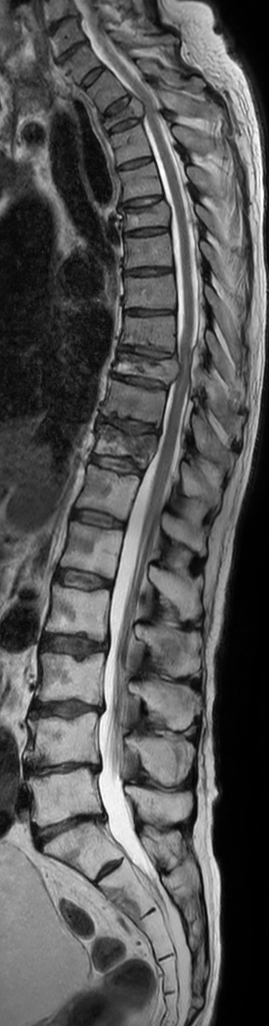

Patient with metastasis. Compressed SENSE is used to shorten the time on the table for the patient. The total spine T2w mDIXON sequence covers both the thoracic and lumbar spine in only 5:20 minutes, providing different contrast (Water only + In Phase). Compressed SENSE is also integrated in all other sequences to reduce scan time without losing image quality.

Sagittal T2w mDIXON XD TSE (Water only)

Sagittal T2w mDIXON XD TSE (In Phase)